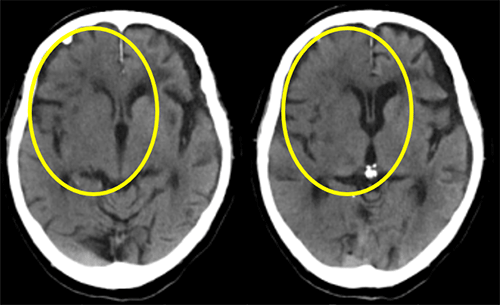

Fig.6にRevolution Ascend導入前後の同一患者における比較画像を提示します。

Noise Indexはどちらも2.5に設定しており、AscendのTFI画像はVCTと比較して被ばく線量はおよそ2割減少していますが、ざらつきの無い、ノイズが低減された画像が得られました。前述の通りTFI画像は、高線量FBP画像の教師データから作成されています。このため、従来のFBP画像と遜色ない高画質な画像作成が可能となります。

特に脳幹レベルは骨に囲まれているためアーチファクトやノイズが多く、評価が難しい場合がありましたが、TFI画像では頭蓋骨からのアーチファクトも減少しています。またノイズが取り除かれたことによって実質レベルでもコントラストが向上しています。頭部などの密度分解能が重要とされる領域での読影負担軽減、診断能の向上に貢献しています。このように、高画質で高品質な印象を与えるTFI画像処理は、画質低下因子を解消し、臨床応用に大きなメリットを与えることができます。

Fig.6 従来機種とRevolution Ascendの比較

症例①右中大脳動脈領域にEarly CT signを認めたため、血栓溶解薬による治療が行われた。

症例②左中大脳動脈領域にHyperdense MCA signが認められる。

Revolution AscendのTFI画像では、従来機種(VCT)比べと比較してもノイズ成分除去されつつ違和感のない画像が得られました。医師からも上記のような症例の場合おいても迷わず読影でき、すぐに治療に移行することが出来たとの評価を受けています。